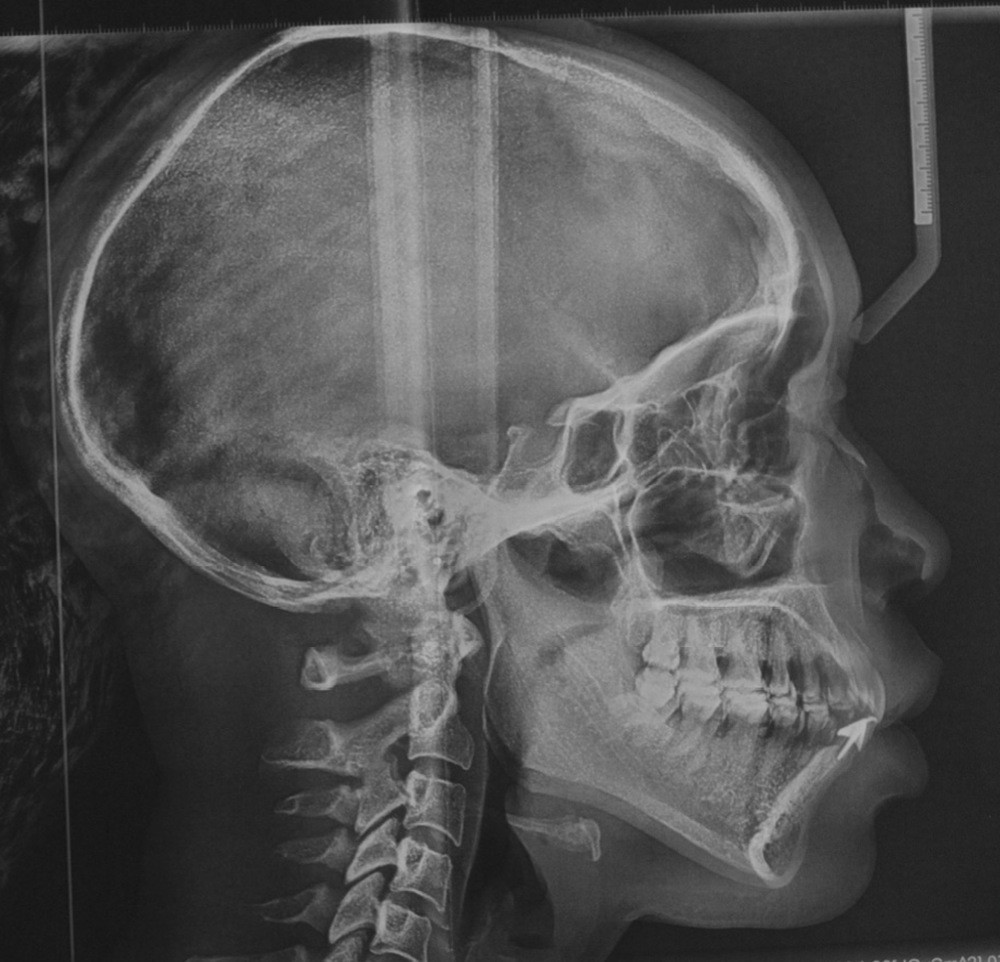

L’analyse céphalométrique de profil révèle des rapports de classe II de Ballard par prognathie maxillaire sur un schéma facial normodivergent associés à une forte proalvéolie mandibulaire (IMPA : 108°) et une légère retroalvéolie maxillaire (I/FH : 108°) (fig. 9 et 10).